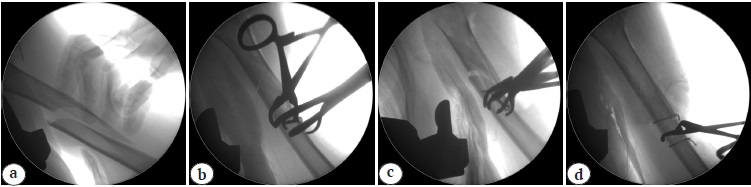

A 73-year-old patient applied to the European Clinic of Sports Traumatology and Orthopaedics (Mocow) 4 days after the injury resulting from a fall on the left upper limb. An X-ray examination was performed on admission, a multi-fragment fracture of the proximal and middle thirds of the humerus was diagnosed (Fig. 1). Additionally, signs of neuropathy of the left radial nerve and secondary anemia due to blood loss (hemoglobin of 110.0 g/L, erythrocytes of 3.53×1012/L, and hematocrit of 32.10%) were detected.

Fig. 1. X-rays of the left shoulder at admission: multi-comminuted fracture of the proximal and middle thirds of the humerus, dislocation of the humeral head